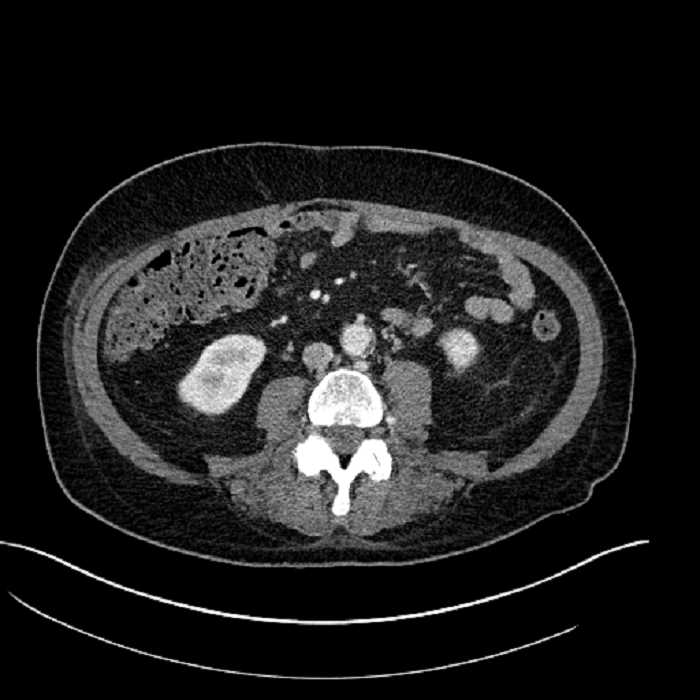

• Mild mural thickening of a segment of the sigmoid colon with adjacent fat stranding and a 1.5 cm fluid and gas collection along the tip of an inflamed diverticulum

• Loss of the normal fat plane between this collection and adjacent loops of small bowel, which demonstrate mural thickening

• No bowel obstruction

• Incidental splenule

Acute sigmoid diverticulitis complicated by a small contained perforation and a large abscess in the right hepatic lobe. Additional small subcapsular abscesses along the anterior margin of the left hepatic lobe.

Additionally, loss of the normal fat plane between the peridiverticular collection and adjacent thickened loops of small bowel raises the potential for an enterocolonic fistula.

Hepatic abscess showing the double target sign with low density internally surrounded by a thin inner enhancing rim (red arrow) and ill-defined outer low density rim (yellow arrow). Blue arrow indicates an internal septation. Red arrows: additional smaller subcapsular abscesses. Red arrow: focal contained perforation associated with diverticulitis.